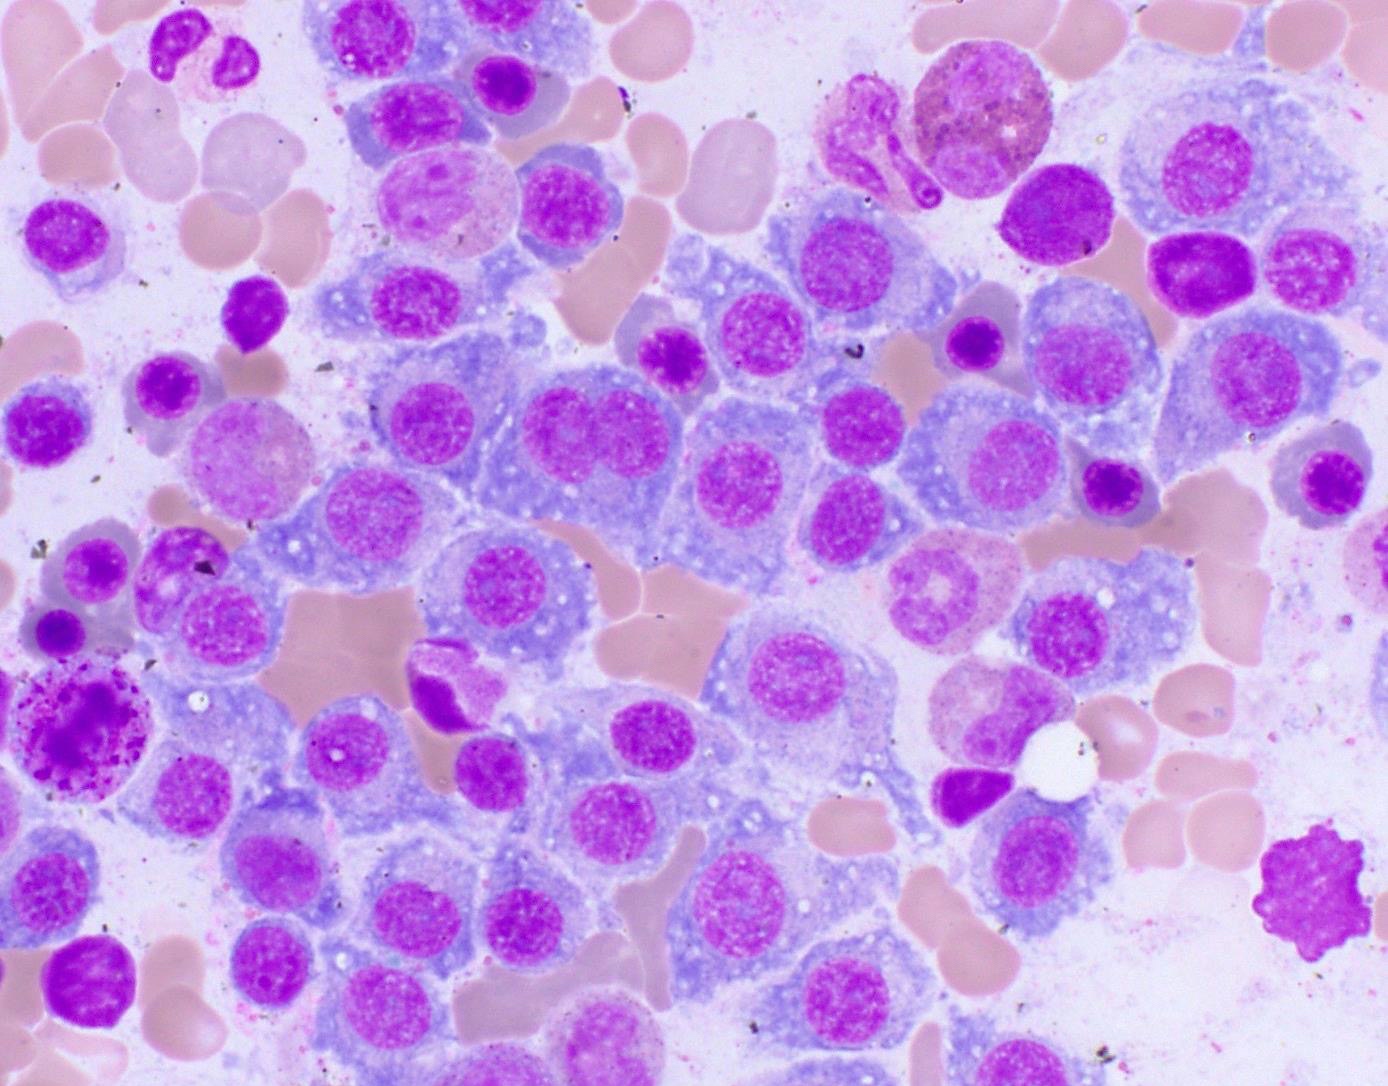

Cytology description

- Cytology can assess plasma cell morphology (e.g., mature, immature, plasmablastic) but number of plasma cells present may vary substantially from the core biopsy

- Mature plasma cells: oval with abundant basophilic cytoplasm, perinuclear hof, round eccentric nuclei, clock face chromatin and indiscernible nucleoli

- Immature plasma cells: higher nuclear to cytoplasmic ratio, more abundant cytoplasm and hof region compared to plasmablastic, more dispersed chromatin, often prominent nucleoli

- Plasmablastic: less abundant cytoplasm with little or no hof region, fine reticular chromatin, large nucleus (> 10 microns) or large nucleolus (> 2 microns) (Blood 1998;91:2501)

- Pleomorphic: multinucleated, polylobated

- Rare cases may have small, lymphoid appearing plasma cells or plasma cells with marked nuclear lobation

- Immature or pleomorphic features are rare in reactive plasma cell proliferations

- Morphologic features:

- Mott cells / morula cells: multiple grape-like cytoplasmic inclusions comprised of crystalized immunoglobulin

- Russell bodies: hyaline intracytoplasmic inclusions

- Flame cells: vermillion staining glycogen rich IgA in cytoplasmic projections (American Society of Hematology: Flame Cells in Multiple Myeloma [Accessed 26 May 2022])

- Pseudo-Gaucher cells / thesaurocytes: overstuffed fibrils (J Clin Pathol 1976;29:916)

- Cytoplasmic crystals: occasional in myeloma, common in adult Fanconi syndrome (Am J Clin Pathol 1983;80:224)

- Dutcher body: pale staining immunoglobulin filled cytoplasm invaginating into the nucleus and appearing as an intranuclear inclusion, single and usually large, more common in IgA myeloma